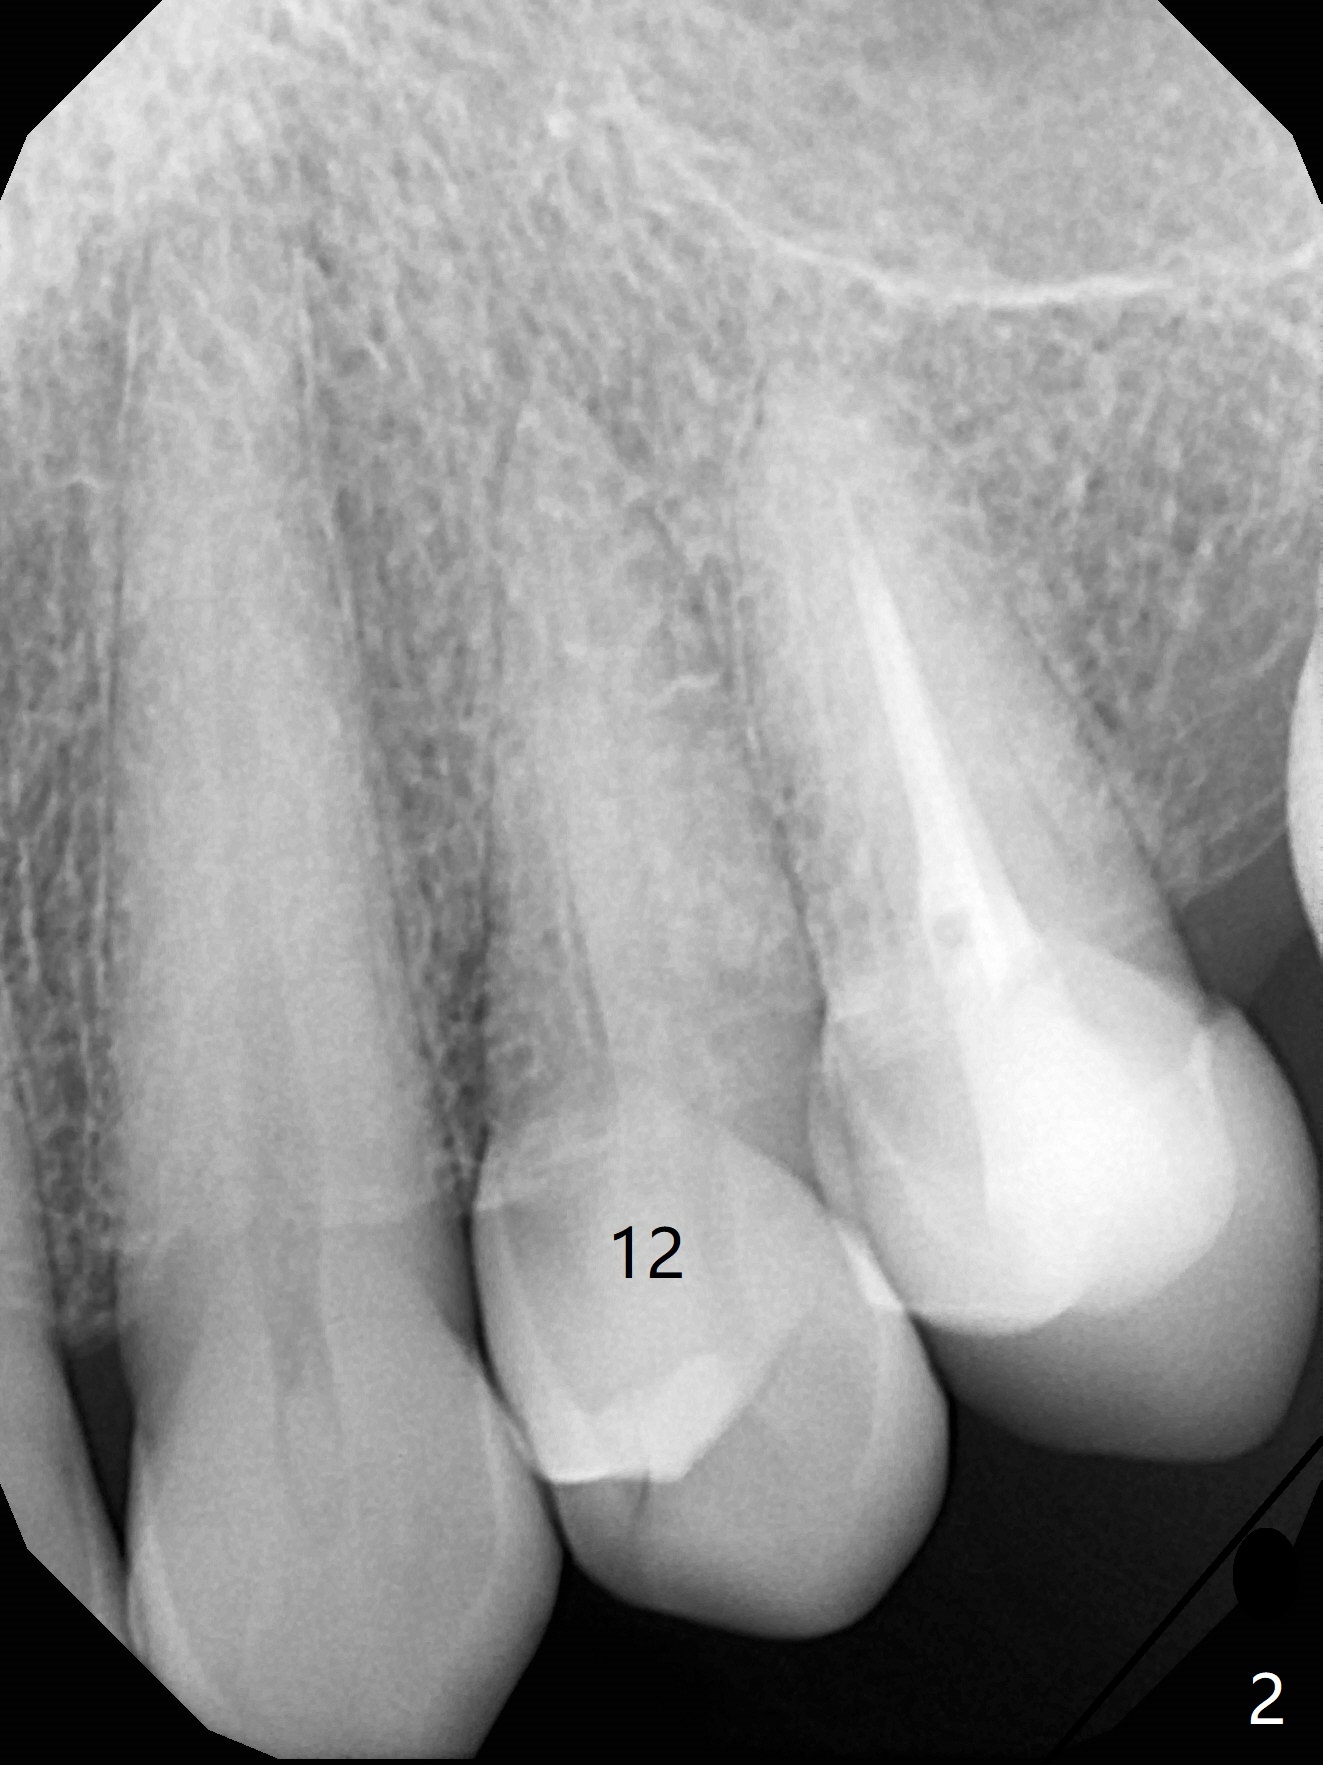

Tooth Crack: Emergency

A 57-year-old woman presents to clinic when her ex-dentist is too busy to place immediate implant for a crack tooth at #12 (Fig.1,2). Free hand placement is scheduled in 2 days. Because of loss of several molars, the occlusal clearance for the immediate provisional should be sufficient (Fig.3). Prepare 4 or 4.5 x17 or 20 mm Tatum implants. Take photos of the crack before surgery.